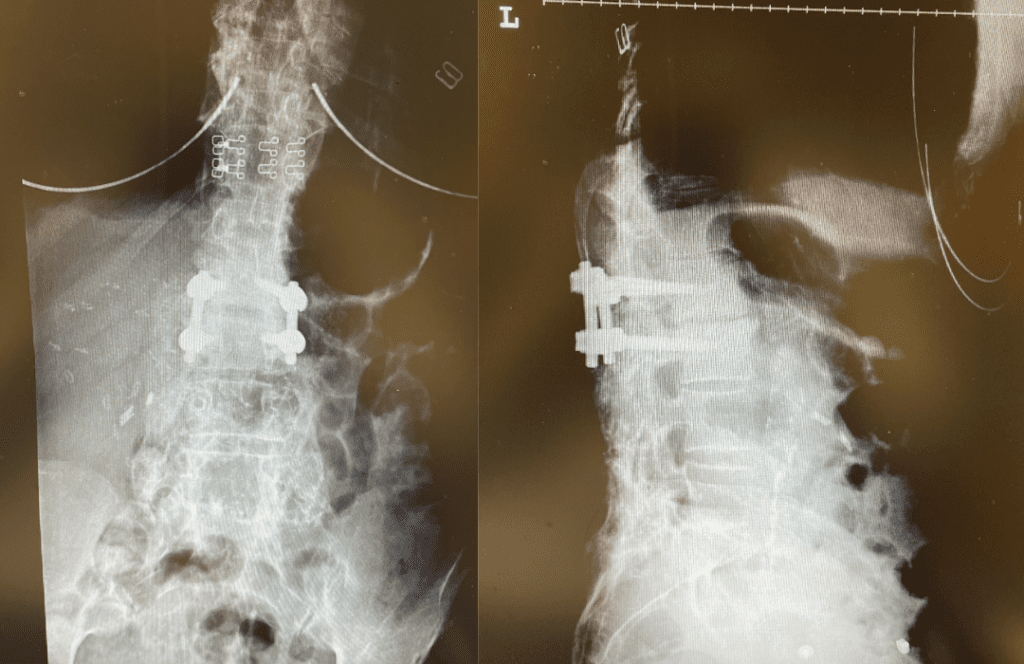

During the decompression we removed the inferior facets of L2 after the L3 screws were removed. This is a key maneuver in a revision decompression as it allows access to a dissection plane that allows the foramina and both L3 nerve roots to safely be decompressed. The L2 lamina is removed as well as a dissection plane at the inferior aspect of the bone is developed with an up biting curette. Because of her solid fusion it was only necessary to add new screws at L2 and L3 giving her a shorter construct and less potential stress at the next segment. Post operatively the patient did very well with resolution of leg pain and improved strength in her proximal leg strength. (Figure 3)

Figure 3. Post Op AP and lateral x-rays after L2-3 instrumented fusion